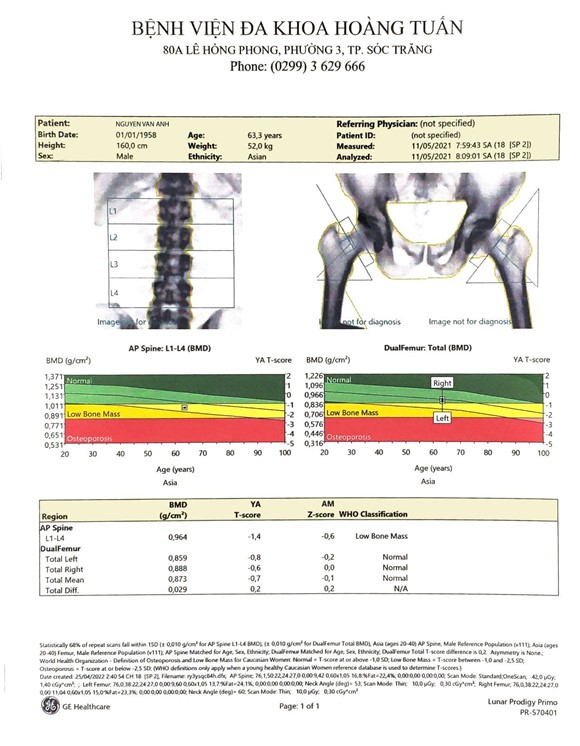

Phiếu trả kết quả tầm soát loãng xương của một bệnh nhân tại Bệnh viện Đa khoa Hoàng Tuấn bằng công nghệ DXA được đo tại nhiều vị trí bao gồm cổ xương đùi 2 bên, cột sống thắt lưng và các thông số liên quan.

Ngoài chẩn đoán loãng xương, hiện tại Bệnh viện Đa khoa Hoàng Tuấn còn cung cấp kết quả về dự báo nguy cơ gãy xương trong 10 năm miễn phí cho quý khách hàng đến tầm soát loãng xương tại bệnh viện, để quý khách không chỉ biết được tình trạng sức khoẻ xương hiện tại mà còn cung cấp cho khách hàng thông tin về khả năng gãy xương trong tương lai để có cái nhìn chung và phòng ngừa các biến chứng của loãng xương một cách tốt nhất.